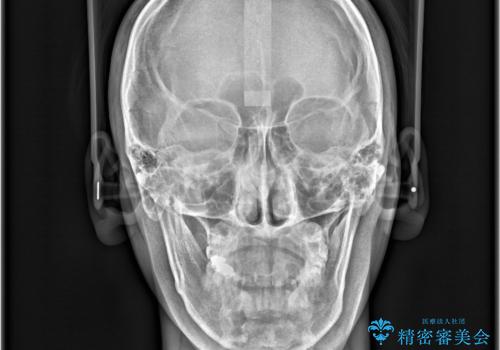

- 「上の前歯の捻じれと下の前歯のでこぼこを治したい」を主訴に来院された患者様です。

矯正検査の結果、非抜歯で矯正可能だったためインビザラインで治療を行いました。

アーチの拡大とIPRで叢生を改善いました。